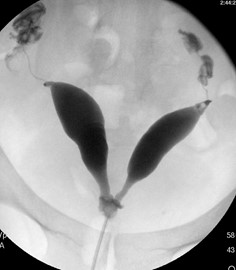

HSG ya da rahim filmi uterus boşluğunu ve fallop tüplerin açık olup olmadığını değerlendirmede kullanılan en geleneksel tanı yöntemidir. Normal uterin kavite üçgen şeklinde, simetrik ve düzgün konturludur ve verilen kontrast madde her iki tüpten geçerek karın boşluğunda dağılır. Tüplerin açık olup olmadığının yanı sıra çeşitli uterin anomaliler, polip ve myomlar, rahim içi yapışıklıklar HSG de karakteristik bazı görünümler oluştururlar.

Özellikle yağda eriyen kontrast madde ile yapılan HSG sonrası izleyen birkaç ay içinde spontan gebelikler gözlenebilir. Tüpler açık olduğu halde yanlışlıkla kapalı ya da daha az oranda kapalı olduğu halde açık gibi görülebilir. Kontrast madde verilirken rahim kasılarak tüplerin proksimal kısımlarında spazma bağlı kapalıymış görüntüsü oluşturabilir. Bu nedenle HSG’de tüpler açık izlenirse gerçekte kapalı olma olasılığı çok düşüktür (<%5), ancak HSG de tüpler kapalı gözüküyorsa yanılma payı yüksektir ve HSG bir- iki ay sonra tekrarlanmalıdır (%60 açık çıkar) ya da Laparoskopi ile tüplerin kapalı olduğu doğrulanabilir.